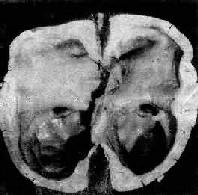

图16-7 海马钩回疝 左海马回内侧肿胀有深切迹(箭头),中脑右移变形,中脑右大脑脚受压,局部坏死出血(Kemohan切迹) 3.小脑扁桃体疝又称枕骨大孔疝。主要由于颅内高压或后颅凹占位性病变将小脑和延髓推向枕骨大孔并向下移位而形成小脑扁桃体疝。疝入枕骨大孔的小脑扁桃体和延髓成圆锥形,其腹侧出现枕骨大孔压迹(图16-8),由于延髓受压,生命中枢及网状结构受损,严重时可引起呼吸变慢甚至骤停,接着心脏停搏而猝死。